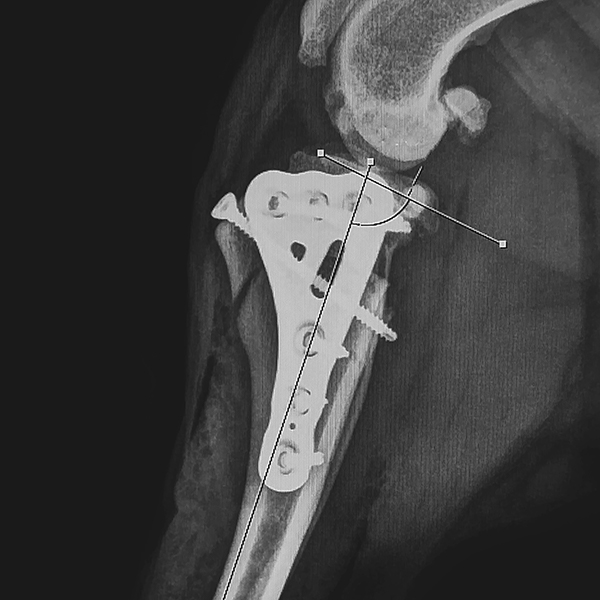

This course will explore the cannulated headless compression screw system, including its design, materials, and surgical applications. Participants will gain insights into the indications for these implants, such as elbow condylar fractures, ununited anconeal process (UAP), and hip procedures.

- Identify appropriate clinical indications for the use of headless compression screws, including elbow condylar fractures, ununited anconeal process (UAP), and hip procedures.

- Demonstrate knowledge of anatomical approaches to the elbow and hip relevant to surgical fixation.